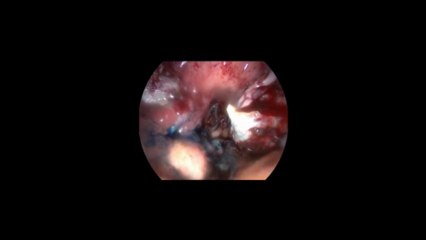

Laparoskopi ile Over kist eksizyonu - Prof. Dr. Aydan Biri

Duration: 12:23